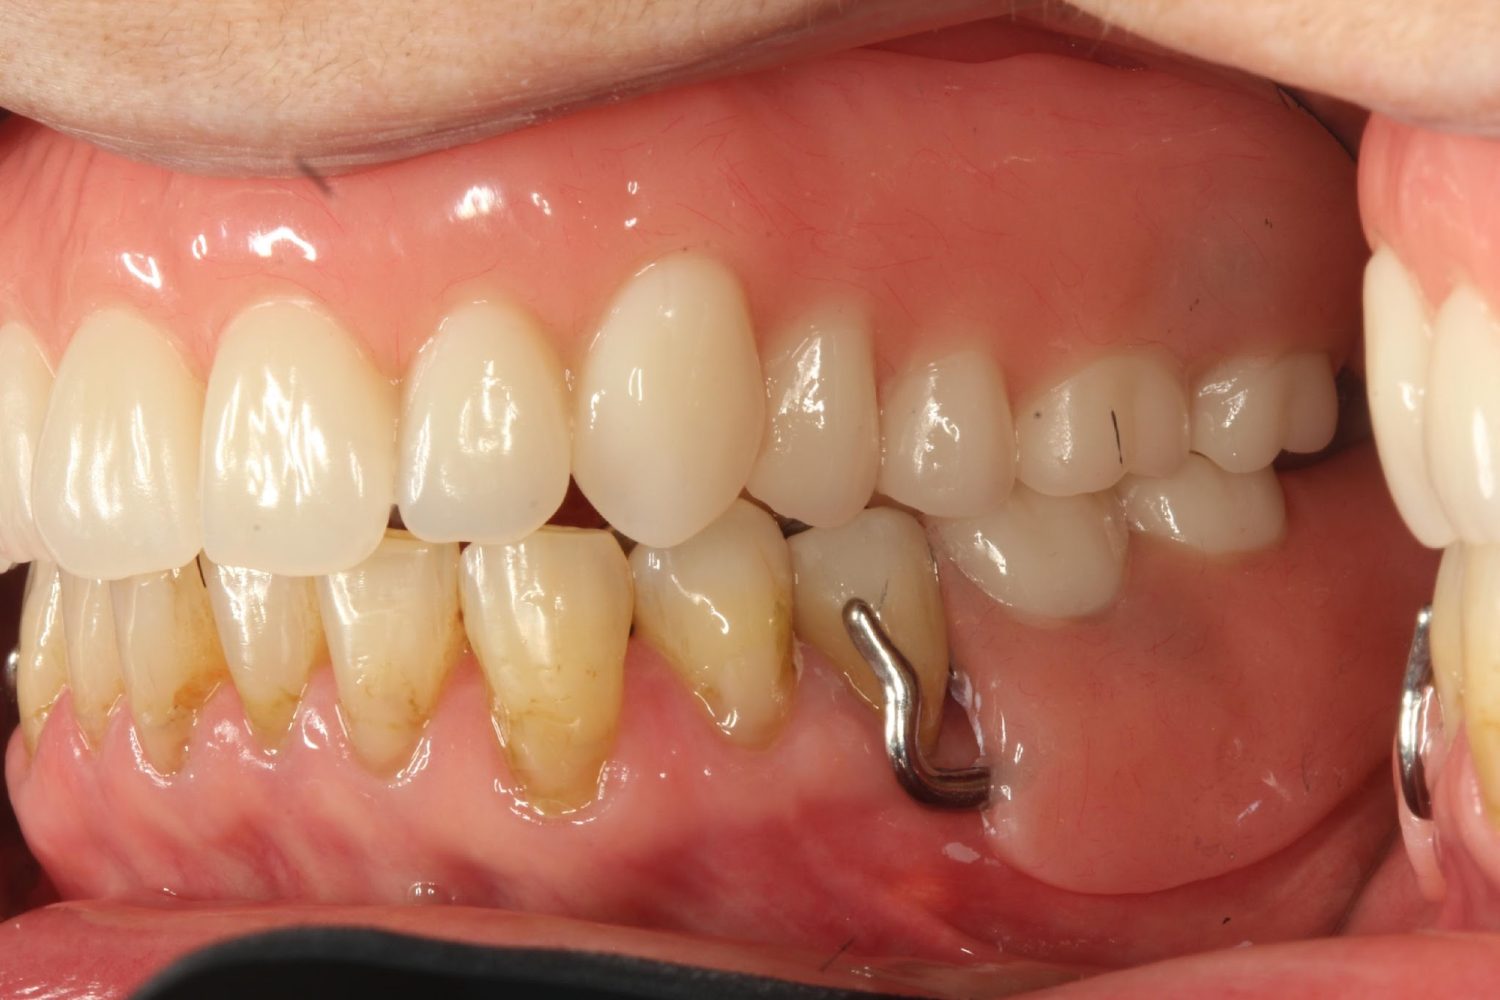

インプラント治療の症例紹介④

Before

After

主訴

義歯による疼痛

治療内容

下顎舌側に骨隆起があり義歯困難な状態。保存不可能な歯の抜歯を行い、インプラントを埋入し咬合再構成を行った。

治療費

2,851,200円(税込)

治療期間

29ヶ月

通院回数

26回

想定されたリスク

※咬合力の強い方なので、予防的にマウスピースの装着が必要。インプラント周囲炎の恐れがありました。

濱 仁隆先生

浜歯科

歯の欠損の対合歯の挺出等を修正し咬合平面を揃え咬合再構成を行った症例。